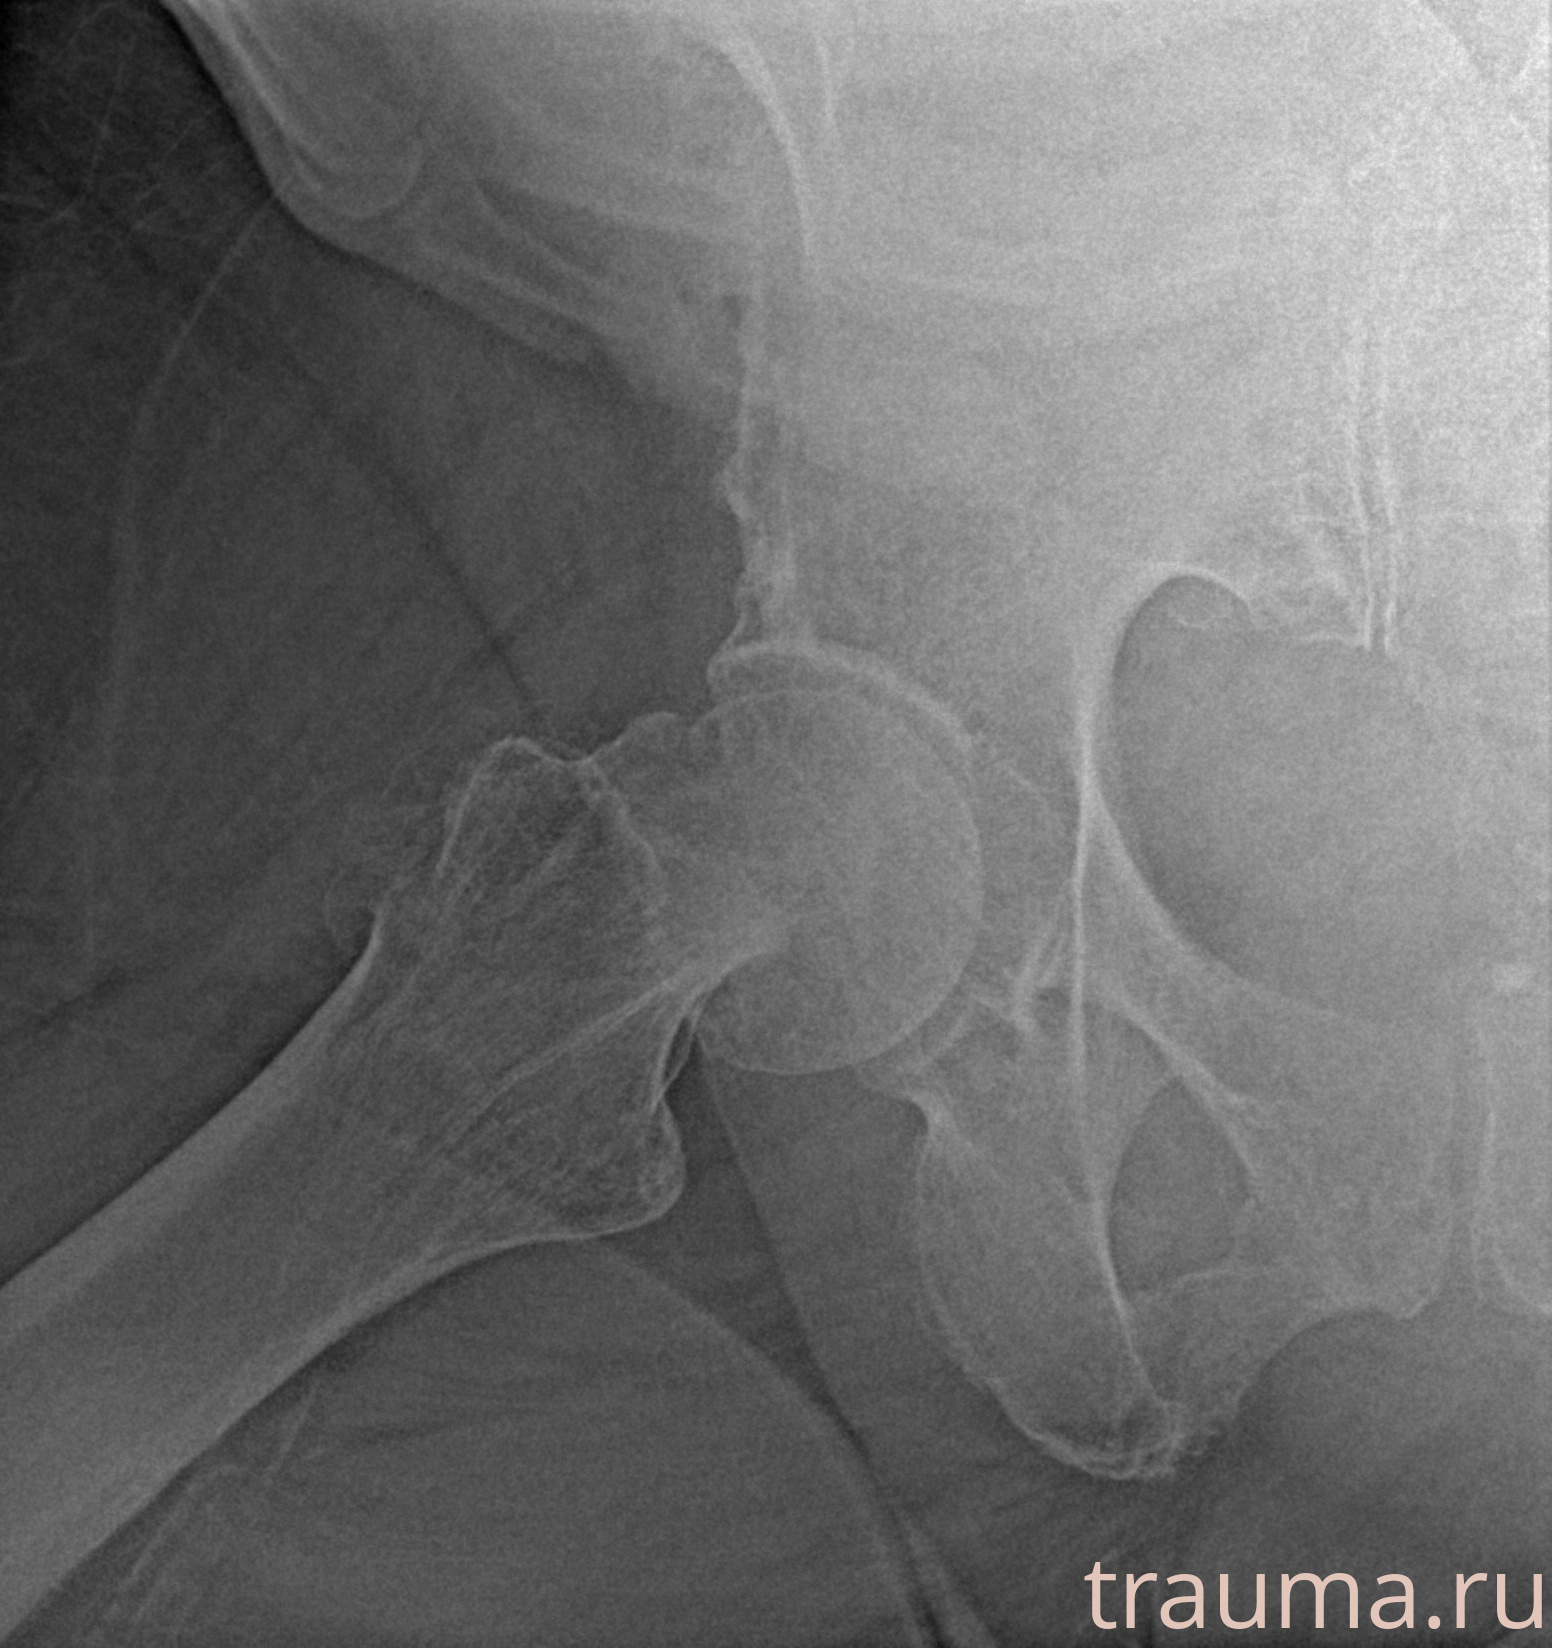

Рентгенограммы

Рентген на дому: по вашему адресу приезжает врач-рентгенолог, травматолог-ортопед с мобильным рентгеновским аппаратом, проводит диагностику травмы или заболевания, делает необходимые рентгенограммы, дает рекомендации по дальнейшему лечению. Получить качественные снимки в домашних условиях возможно благодаря уникальной методике, разработанной МосРентген Центром для института  Склифосовского